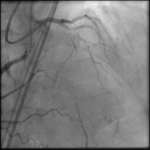

A 64-year-old man presented with angina chest pain and dyspnea on exertion. Stress MPI showed anterior, apical, and septal ischemia. Coronary angiogram revealed 2V CAD (Prox LAD CTO bifurcation with…